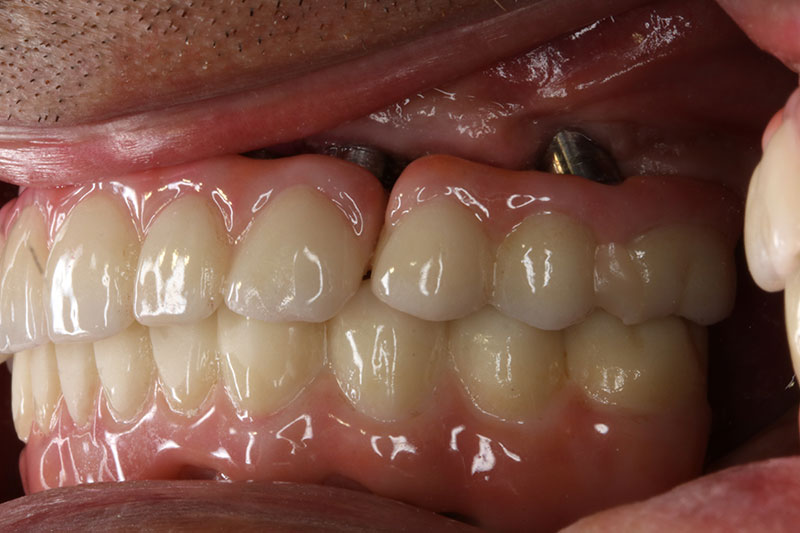

銀髮族植牙 全口植牙重建

案例二

術前

術後